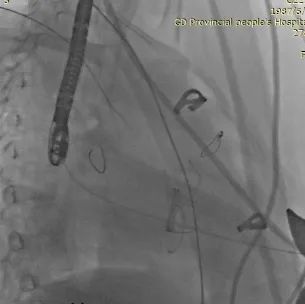

术中TEE&DSA影像:

TEE&DSA引导下进入加硬导丝建立轨道

DSA&TEE引导下J-Valve定位件展开,瓣膜自膨后形态、位置良好